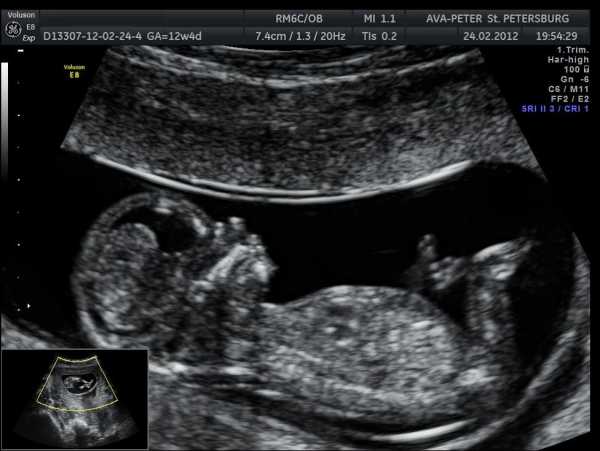

В начале месяца будет проведено исследование на кресле и забор мазка на флору, могут быть дополнительно назначены анализы крови. Плановые УЗИ уже все пройдены, но врач в случае сомнений или опасений может назначить дополнительные УЗИ или проведение доплерографии, КТГ плода. Это поможет в выборе тактики в родах и решении вопроса о том, естественными они будут или показан операция кесарева сечения.